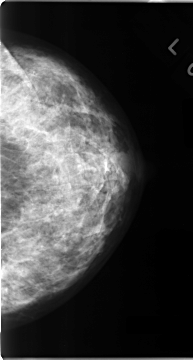

C_0098_1.LEFT_MLO

LEFT_MLO LINES 4712 PIXELS_PER_LINE 2496 BITS_PER_PIXEL 12 RESOLUTION 50 NON_OVERLAY